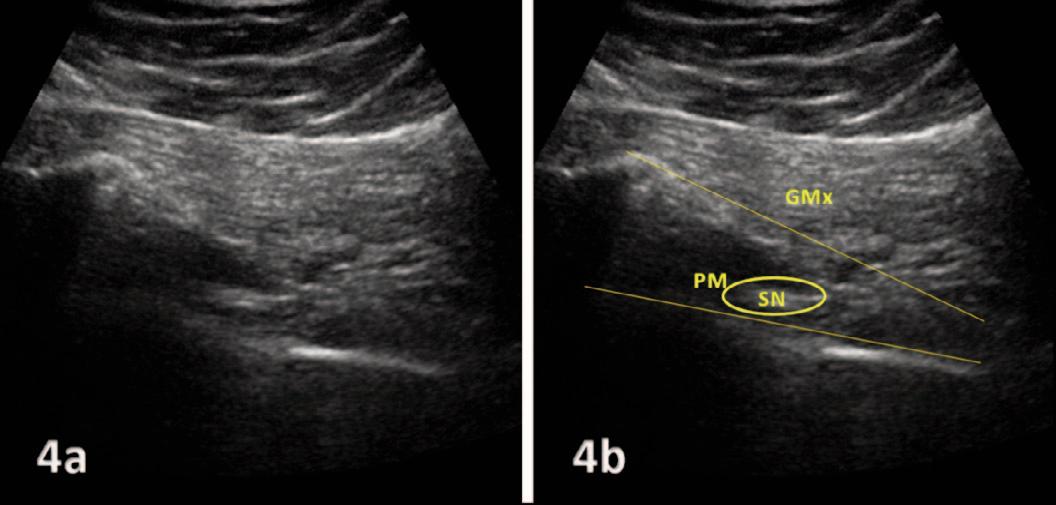

768 Use of Diagnostic Musculoskeletal Ultrasound in the Evaluation of Piriformis Syndrome: A Review for Rehabilitation Providers.

Manske RC, Wolfe C, Page P, Voight M, Bardowski B.